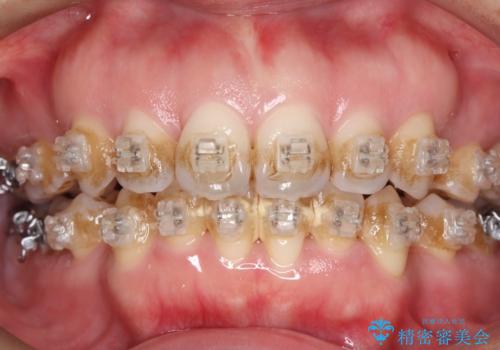

- ワイヤー矯正中の患者様です。

装置の周りの着色が気になるとのことで、エアフローを行いました。。

「着色が取れて、笑うのが楽しみになりました!」

歯面が滑らかになり、清潔感がアップ。

エアフローは定期的に行うことで、より健康的な口腔内を保つことができます。